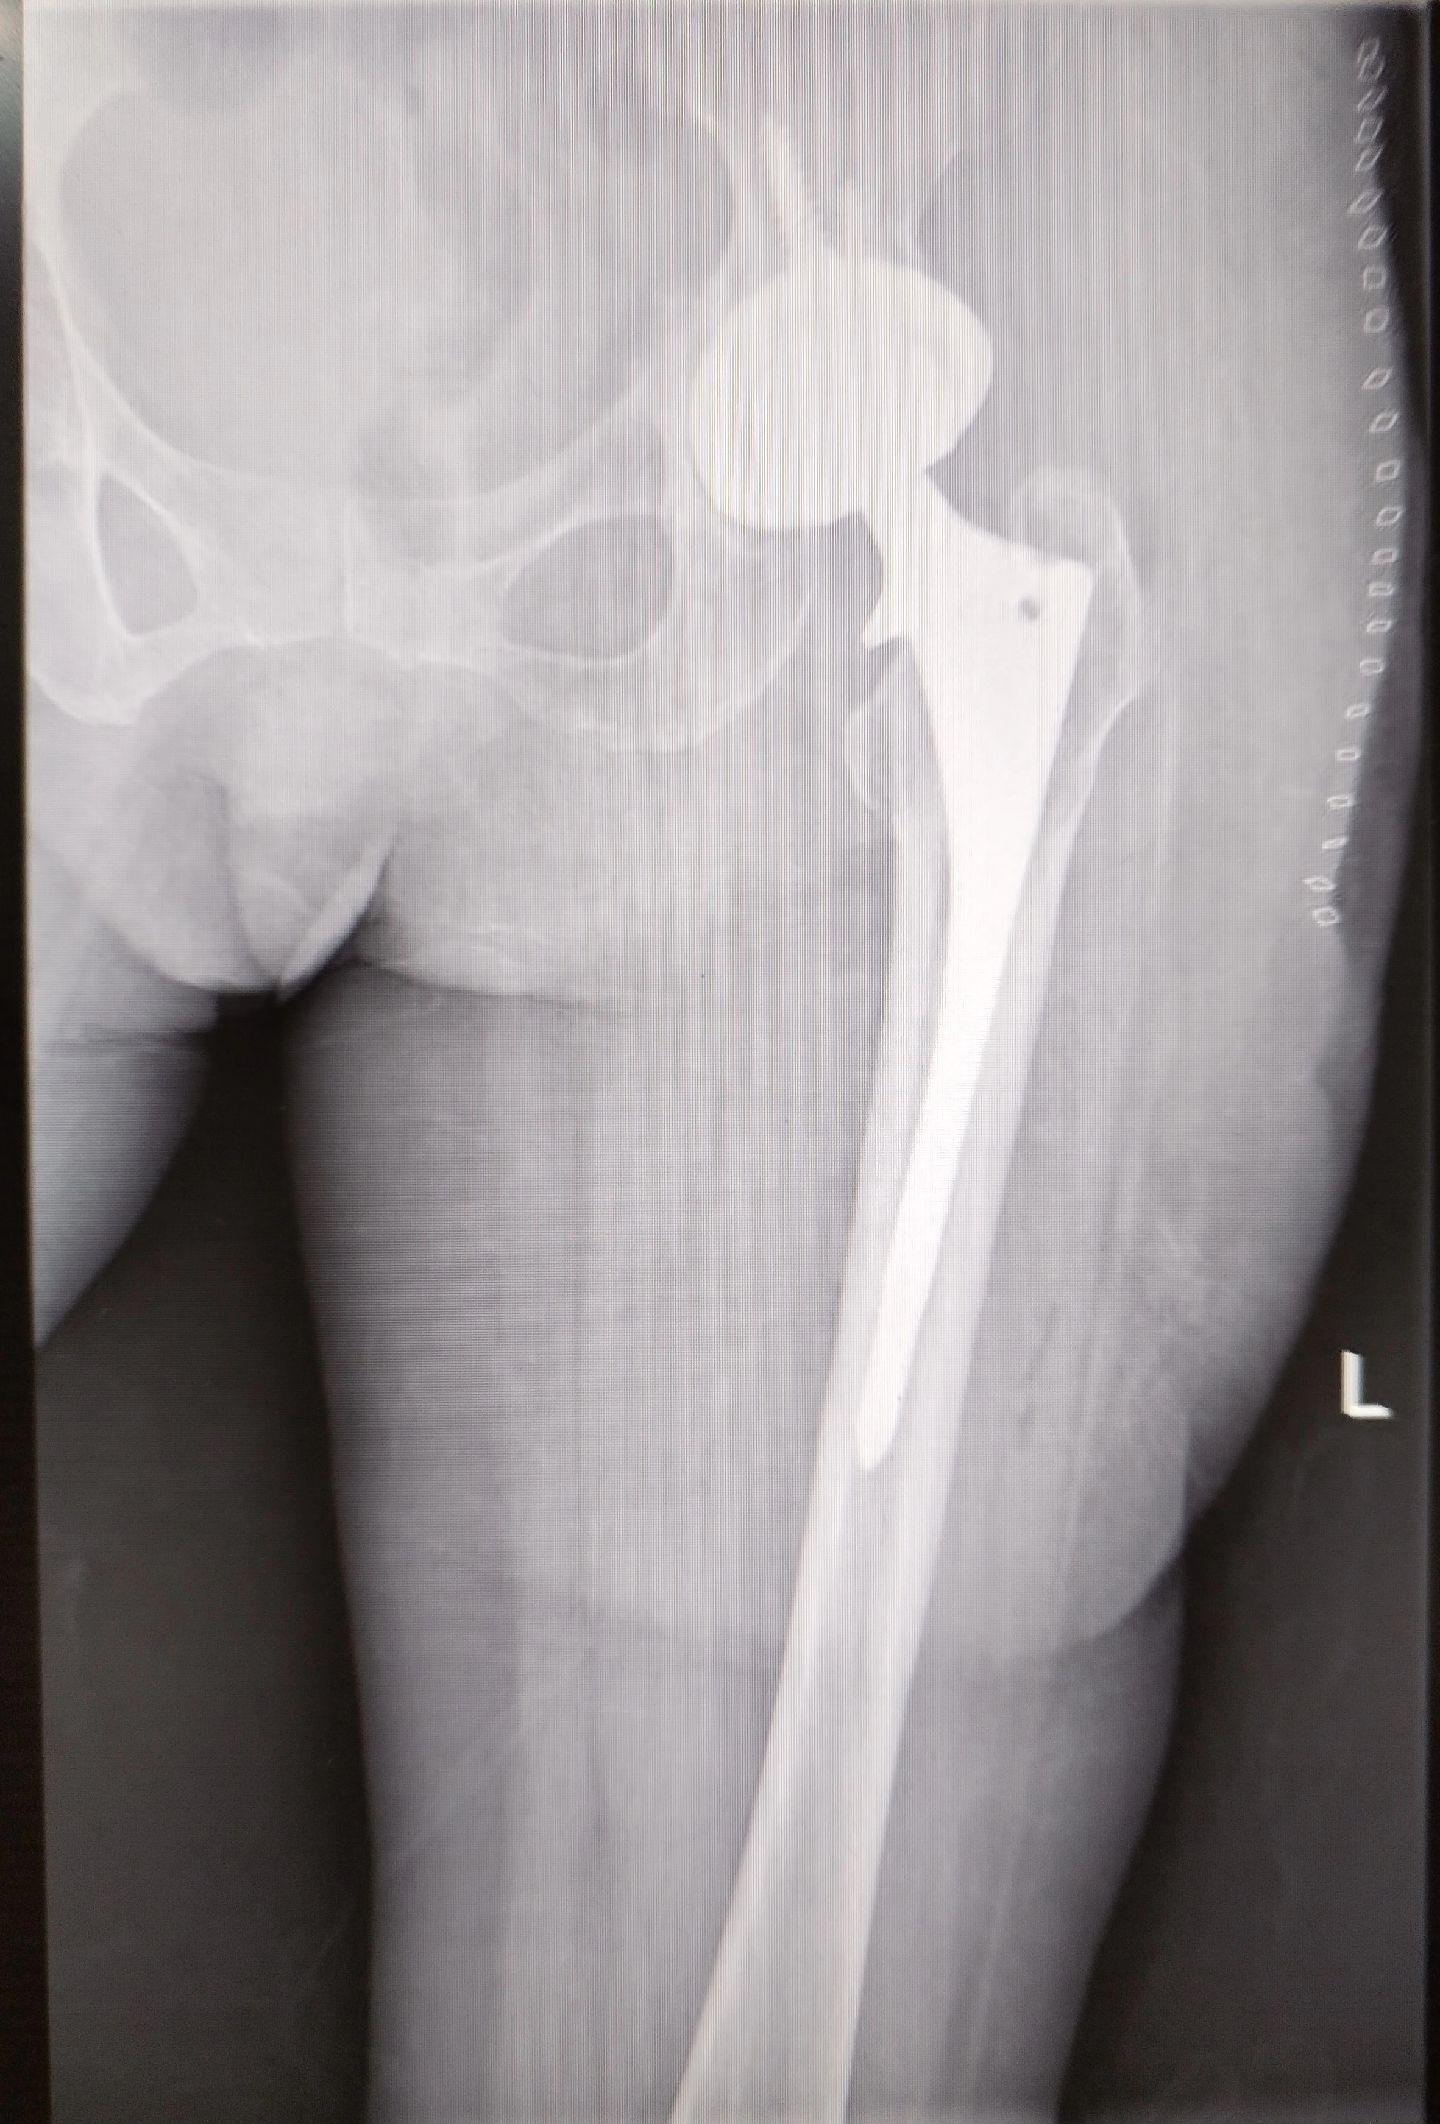

髋关节翻修。髋关节置换术后(外院)4年,磨损颗粒导致的无菌性松动,一期翻修,2天下床活动。磨损有好多因素,材质、体重、活动量等等。